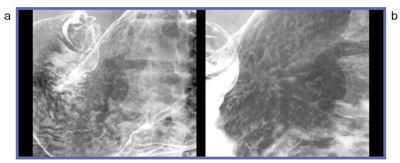

以上のような特長により,デジタル装置は検診に貢献しているが,I.I.-DRの画質,特に解像度に満足していない人もいるように思う。

そこで,登場するのがFPD搭載デジタルX線テレビ装置である。図3,4は同一受診者の比較画像であるが,I.I.(a)に比べ,FPDの画像(b)の解像度が向上していることがわかる。また図5aは,一見すると,陥凹境界が明瞭であり,それに随伴する帯状隆起ということでは,未分化型癌のように見えるが,拡大してみると(図5b)正常粘膜よりも粒の小さな顆粒状陰影が観察され,辺縁に薄く染み出し所見が認められることから,分化型癌であることがわかる。100万画素I.I.では,このような細部の描出は難しい。